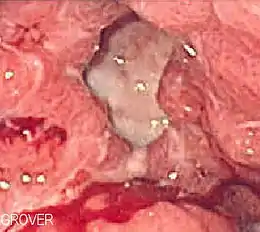

An esophagogastroduodenoscopy (EGD), a form of endoscopy, also known as a gastroscopy, is carried out on people in whom a peptic ulcer is suspected. It is also the gold standard of diagnosis for peptic ulcer disease.[14] By direct visual identification, the location and severity of an ulcer can be described. Moreover, if no ulcer is present, EGD can often provide an alternative diagnosis.

Early endoscopic therapy can help to stop bleeding by using cautery, endoclip, or epinephrine injection. Treatment is indicated if there is active bleeding in the stomach, visible vessels, or an adherent clot. Endoscopy is also helpful in identifying people who are suitable for hospital discharge. Prokinetic agents such as erythromycin and metoclopramide can be given before endoscopy to improve endoscopic view. Either high- or low-dose PPIs are equally effective in reducing bleeding after endoscopy. High-dose intravenous PPI is defined as a bolus dose of 80 mg followed by an infusion of 8 mg per hour for 72 hours—in other words, the continuous infusion of PPI of greater than 192 mg per day. Intravenous PPI can be changed to oral once there is no high risk of rebleeding from peptic ulcer.[14]